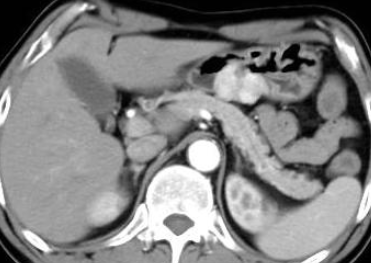

CT图像如下

腹部CT示:胃窦部肿块,形态不规则,腔内生长为主,边界较清晰,邻近粘膜显僵硬;增强后动脉期明显不均匀强化,门脉期、延迟期持续强化。